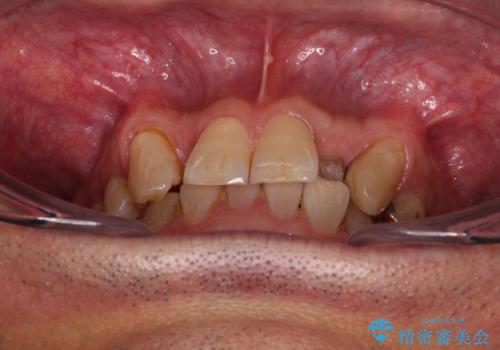

奥歯の欠損と前歯のデコボコを治したい インプラントと矯正治療の総合歯科治療

- 下顎両側の欠損と上顎前歯のデコボコを気にして来院された患者様です。

デコボコは今まで気にせずにいたそうですが、奥歯の欠損改善を機に、矯正治療に興味があるので、相談したいとのことでした。

奥歯に欠損が多く、矯正治療はやや難航することが予想されますが、患者様の希望もあり、上顎左右小臼歯を1本ずつ抜歯し、ワイヤー装置にて矯正治療を行うこととしました。